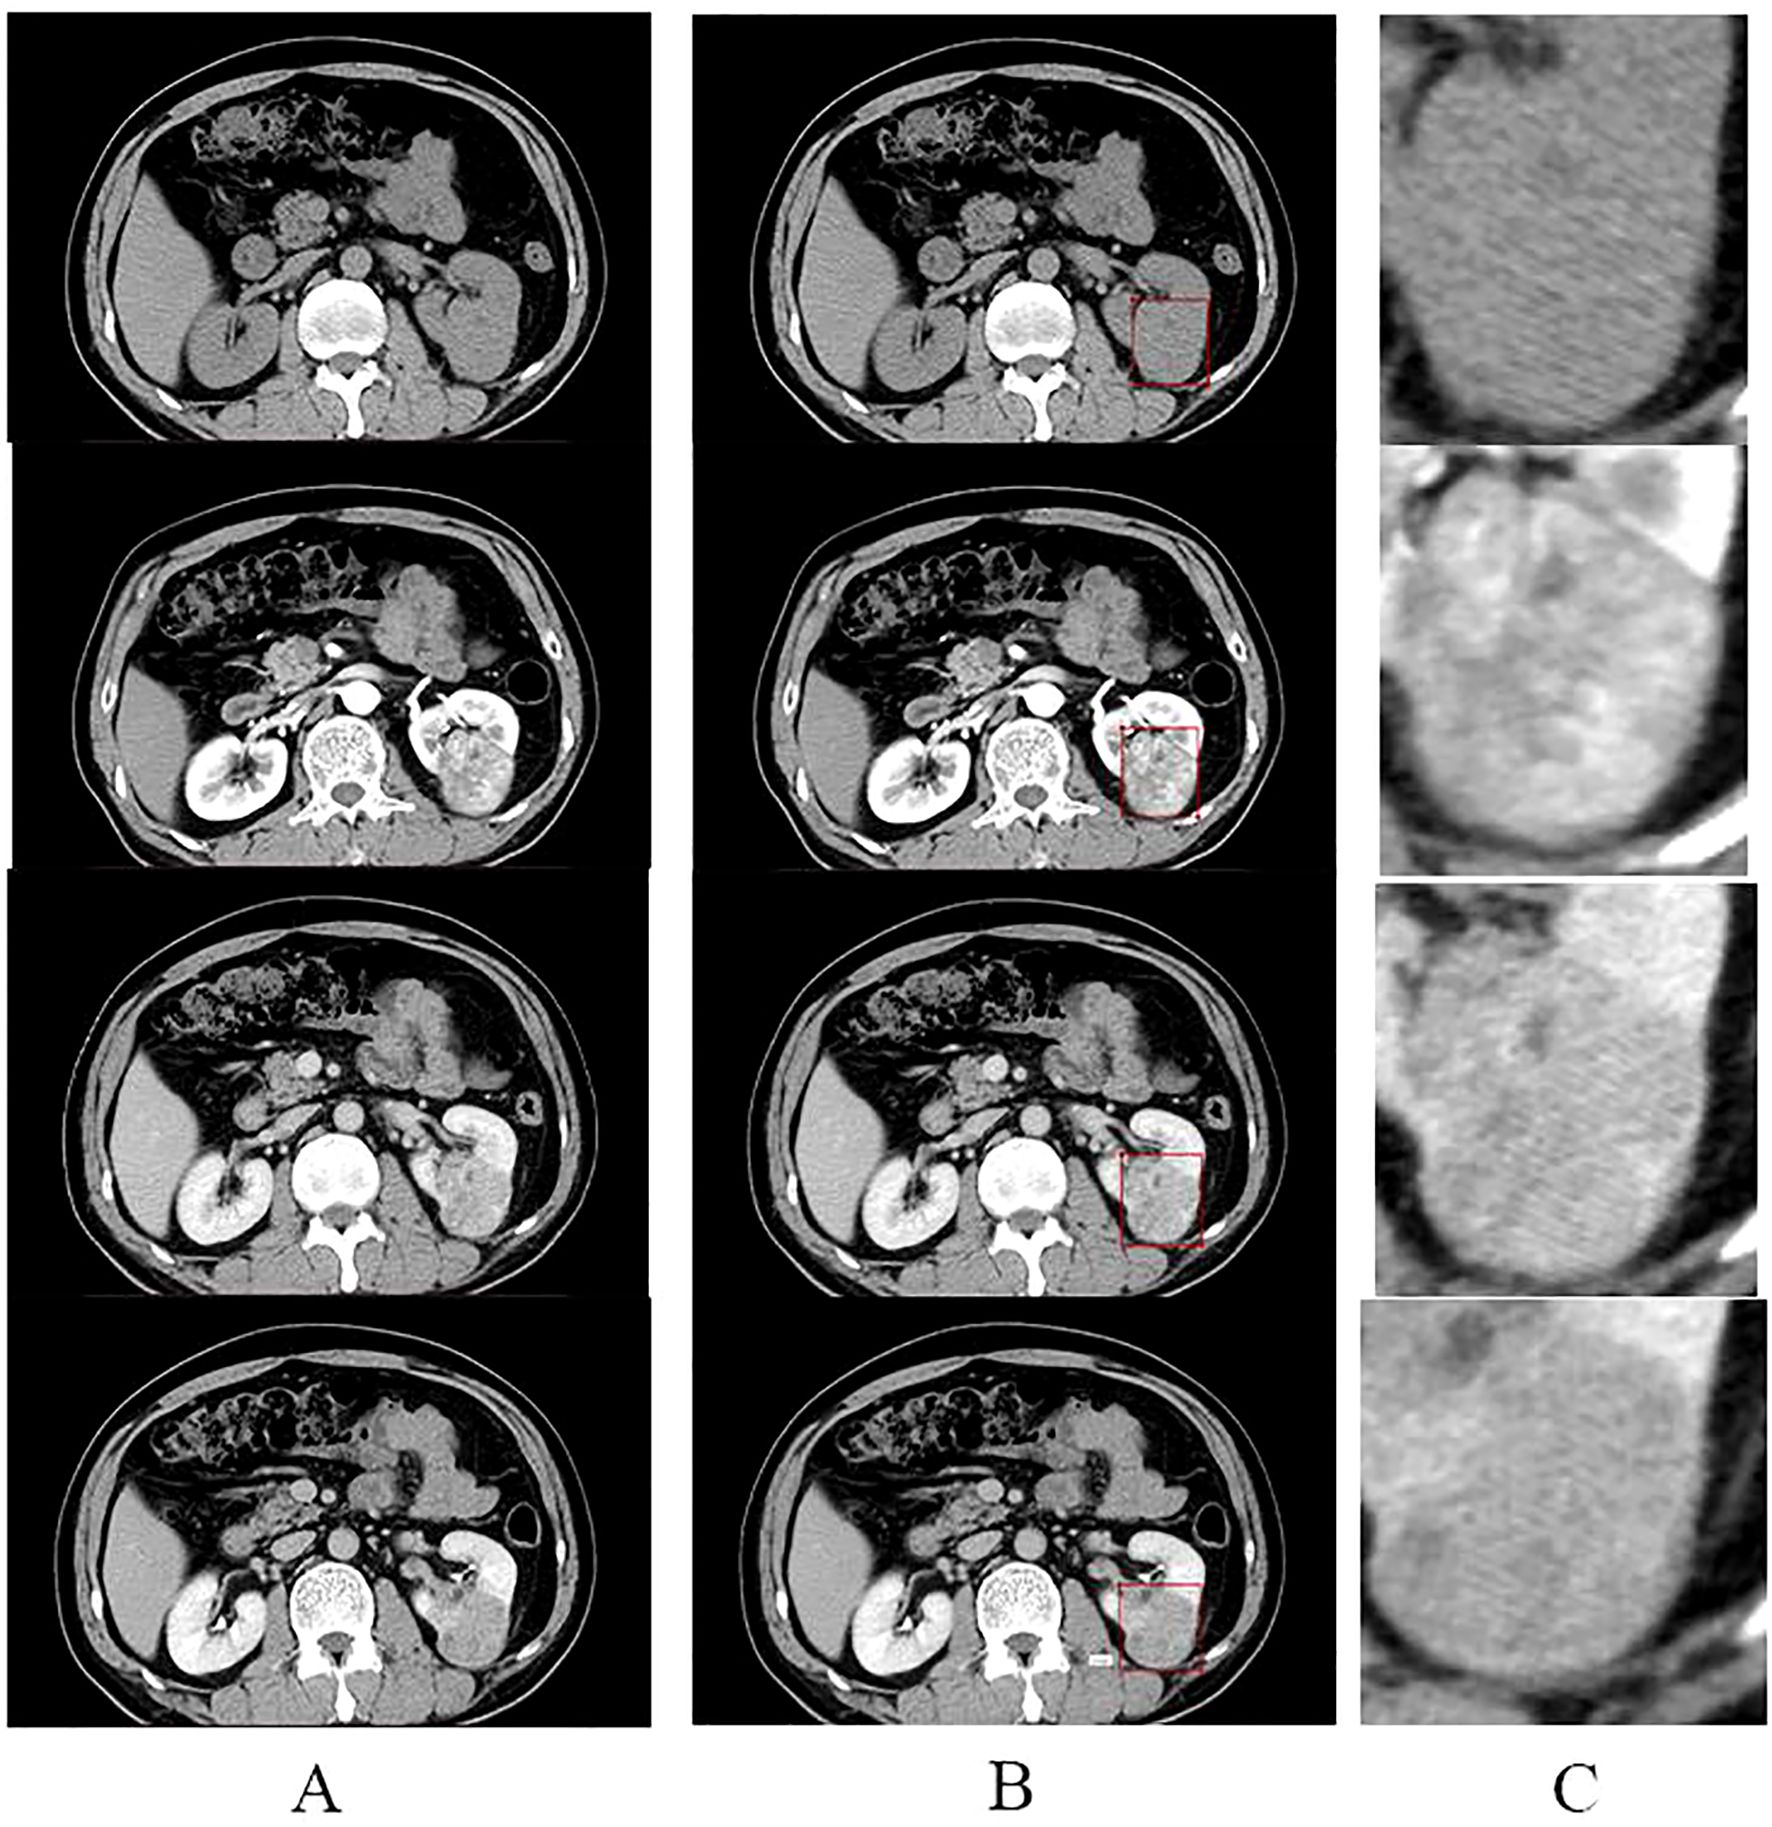

All screened four-stage CT images were loaded into labelm (http://labelme.csail.mit.edu/Release3.0/) and reviewed by two urologists with more than 10 years of experience in urological tumor diagnosis, followed by layer-by-layer rectangular box annotation of the tumor region of interest (ROI), and finally, the generated json file was saved. We opted for rectangular-box ROIs instead of tumor-contour segmentation for reasons of efficiency and clinical practicality. The dataset comprised 5,104 training, 382 validation and 381 test images; using a standardized rule of “expand 1–2 mm beyond the longest diameter”, two senior urologists completed all rectangular annotations within one week with inter-rater reliability ICC > 0.85. By contrast, pixel-level contouring takes 5–10 min per image—more than a ten-fold increase in workload—and is prone to greater inter-observer variability (ICC typically < 0.8). Rectangular boxes can be drawn directly in the clinical PACS without complex algorithms, making the approach easy for clinicians to adopt and facilitating future integration of the model into routine workflow. The criteria for the annotation are as follows: (1) The rectangular box can be delineated by expanding 1-2mm outward with the maximum tumor transverse and longitudinal diameters as the reference. (2) The rectangular box should contain all tumors, and the tumors should be clear; CT images that are unclear should be discarded and not annotated. The images were cropped according to the annotated rectangular box to remove the background information from the non-tumor area to reduce interference(Figure 1). The processed images were resized to 224 × 224 pixels. The consistency of the annotation results was verified by the Intraclass Correlation Coefficient (ICC > 0.85), and consensus was reached through negotiation for inconsistent regions.

Figure 1. Annotation and cropping of four-phase CT images. (A) shows the four-phase CT images of the plain, corticomedullary, parenchymal, and excretory phases, from top to bottom, respectively. (B) shows the corresponding four-stage CT images that have been annotated in the rectangular box. (C) shows images in the center of (C) where the tumor area annotated in the rectangular box of (B) was cropped to remove the background and enlarged.